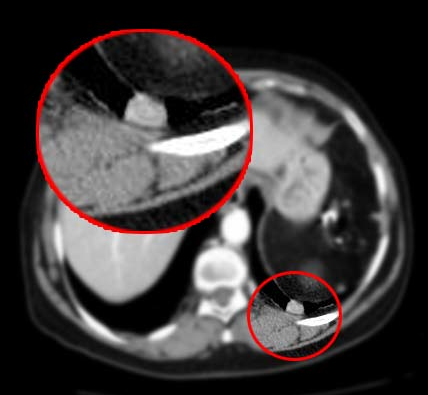

Autotransplante de tecido esplênico no espaço pleural após trauma.

Ocorre após lesão diafragmática/esplênica; cerca de 18% dos casos. Geralmente assintomática e incidental.